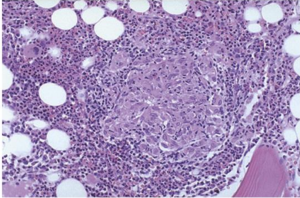

Seorang pria usia 30 tahun datang dengan keluhan demam dan penurunan BB 4 kg dalam 3 bulan terakhir. Pada pemeriksaan fisik didapatkan suhu nya 37.5 C. Pemeriksaan lab mengarah ke anemia penyakit kronis. Biopsi sumsum tulang dilakukan dan gambarannya seperti di bawah ini. Pewarnaan BTA dari jaringan (+). Mikroba penyebab keluhan pria ini dapat dihancurkan dengan mekanisme?